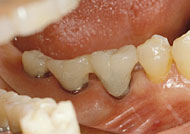

支台部は治癒のバロメーター

これは1ピースは最初から支台部分が口腔内に露出しているため、術直後の感染や咬合に由来した外傷にさらされる危険性と引き替えに、治癒や骨結合度の判定がしやすいという優位性を獲得しているといえるのではなかろうか。なお、術直後の感染や外傷にさらされる危険性といっても、口腔粘膜は基本的に治癒が良く、支台部が最初から口腔内に露出していても感染を起こすことはむしろ稀であることは皆さんもご存知の通りである。 植立後の治癒に影響する要因はいろいろあるが、特に血行の良否は重要な要因である。植立部の顎骨と粘膜が健康で、そこにAQBがきつ過ぎず、すなわち血行を障害せず、デッドスペースもなく植立されれば、基本的に治癒は順調に進むはずである。ただし、喫煙習慣があったり、もともとその局所が慢性硬化性骨炎のように血行の悪い環境にあるような場合、植立後のトラブルを起こすことがあり、これは1ピース、2ピースの共通の大きなテーマなので、別の機会に述べることにする。